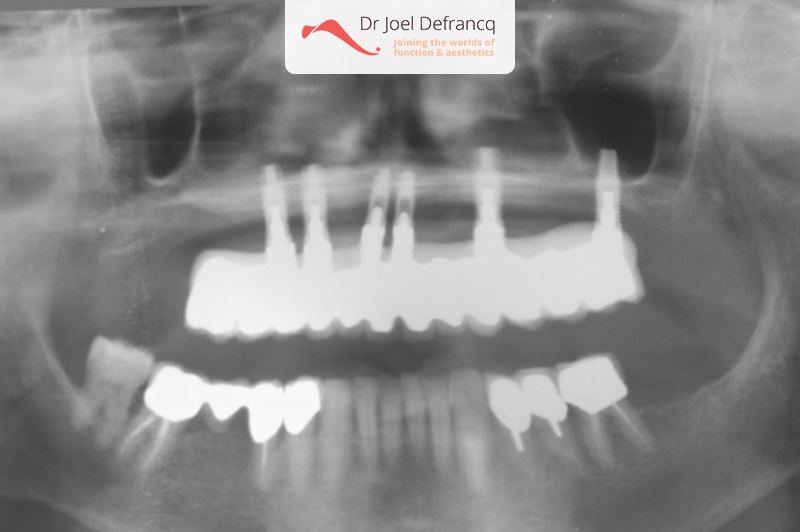

Dentale diagnose

- Open beet

Behandeling tandheelkundige implantaten

- Vaste tanden op implantaten (bovenkaak)